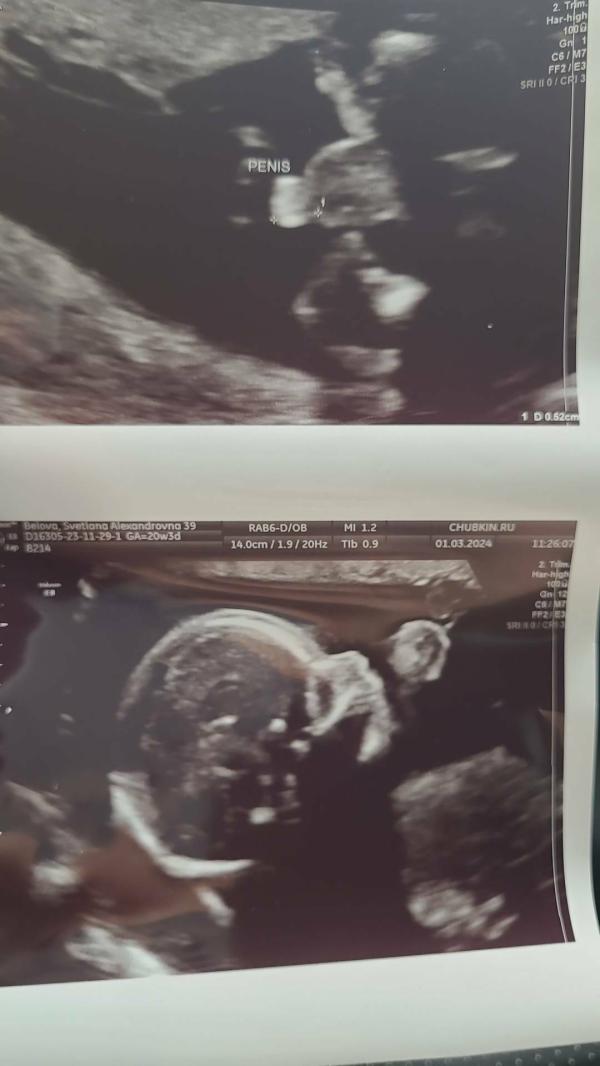

Вчера была на втором скрининге, все хорошо! Малыш растет)) такой скромняшка, прикрывал лицо руками))) и наконец-то мы узнали кто там!))) Не сразу удалось разглядеть, но все же! Третий сын!!! Я аж расплакалась от счастья